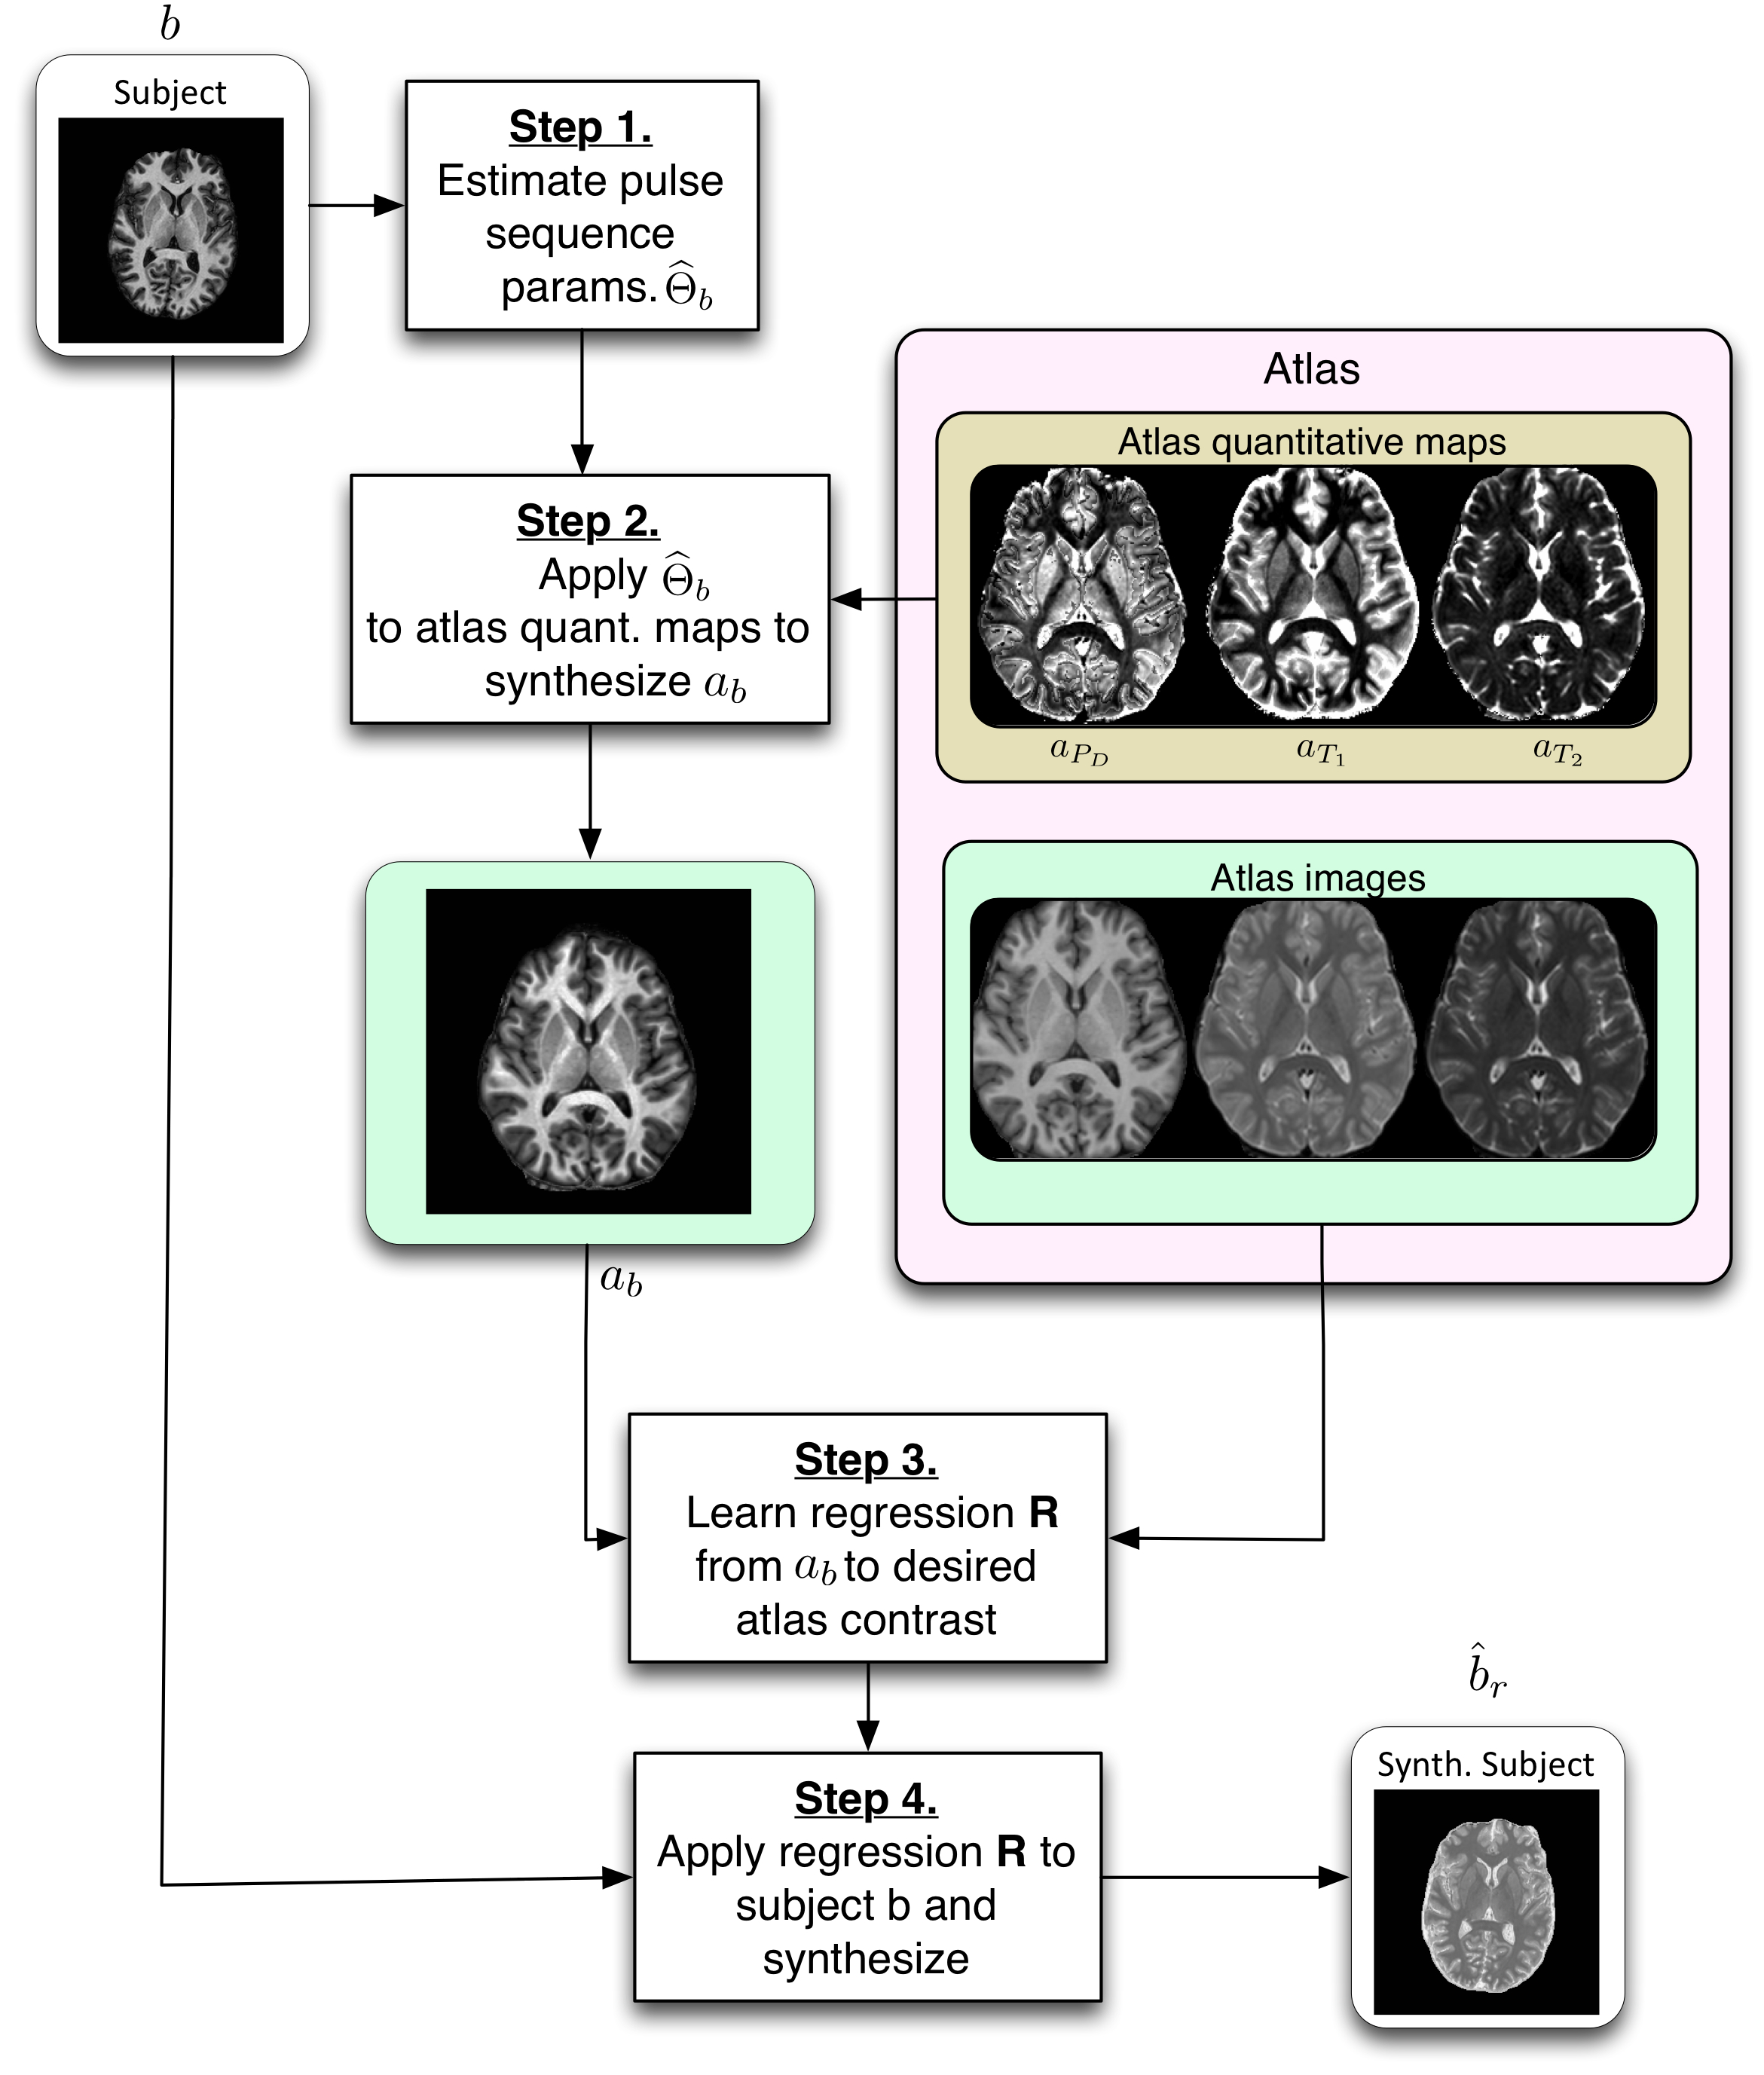

PSICLONE (Pulse Sequence Information-based Contrast Learning On Neighborhood Ensembles) is an image synthesis and intensity standardization framework.

PSICLONE estimates approximate pulse sequence parameters of a given MR image to generate subject-specific training images that are used to train a random forest regression to synthesize a target contrast. The learnt regression is applied to the given image to generate a synthetic or a standardized image.